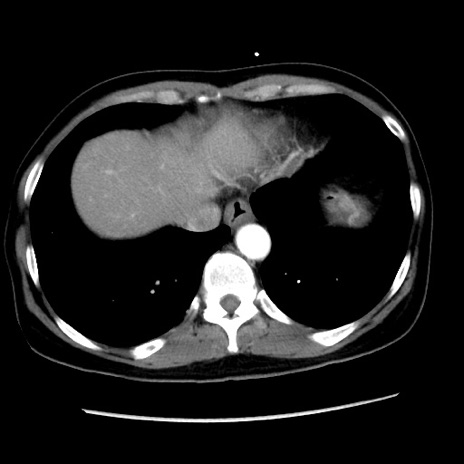

矢状断像